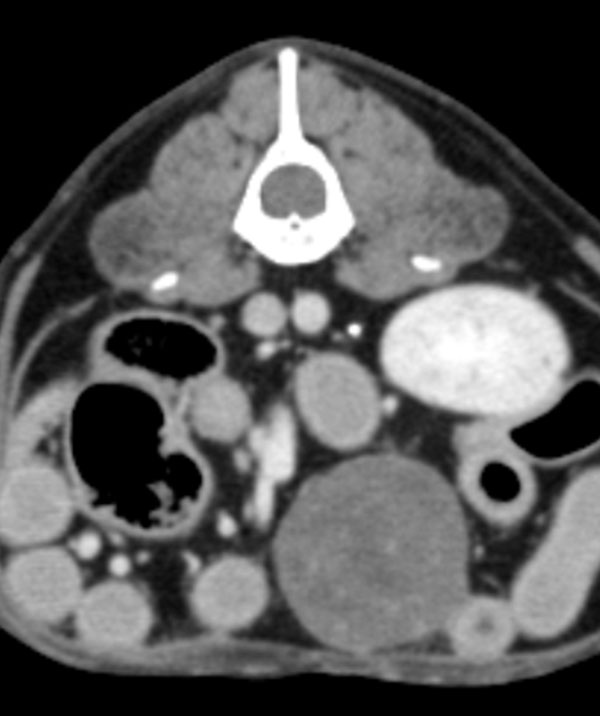

비뇨기 외과(Urological Surgery)는 비뇨기 계통과 관련된 질환을 외과적 방법으로 진단하고 치료하는 분야입니다. 고양이를 포함한 동물들의 신장, 방광, 요도, 외음부 등 비뇨기 계통에 발생한 다양한 질환을 다루며, 이러한 부위의 기능 회복을 목표로 수술적 치료를 제공합니다. 비뇨기 계통에는 소변 생성과 배출을 담당하는 중요한 기관들이 포함되어 있기 때문에, 이들에 발생한 문제는 생활의 질에 큰 영향을 미칠 수 있습니다.